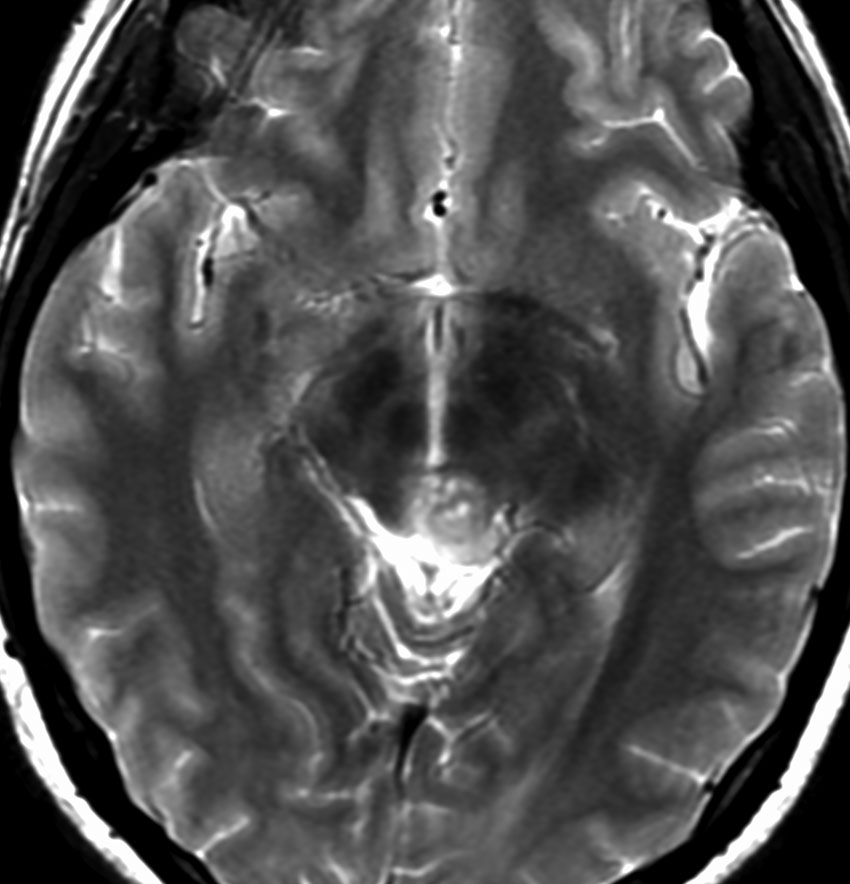

水頭症で発症した6歳児で,4cmくらいある大きな松果体芽腫でした。大学病院で第3脳室開窓術と生検術をして,脳脊髄照射30グレイ(20分割),局所60グレイ(35分割)の放射線治療が行われました。さらにシスプラチンを基剤とした化学療法が3コース行われましたが,放射線で縮小した腫瘍は少し増大してしまいました。

放射線化学療法後の画像です。腫瘍境界は不明瞭(左)で,腫瘍内出血(中央)して,左の視床に浸潤しています。かなりリスクは高いのですが,これを開頭手術で全摘出しました(右),この時点で完全寛解 CR です。この後にさらに化学療法と幹細胞移植(PBSCT,大量化学療法)が加えられました。